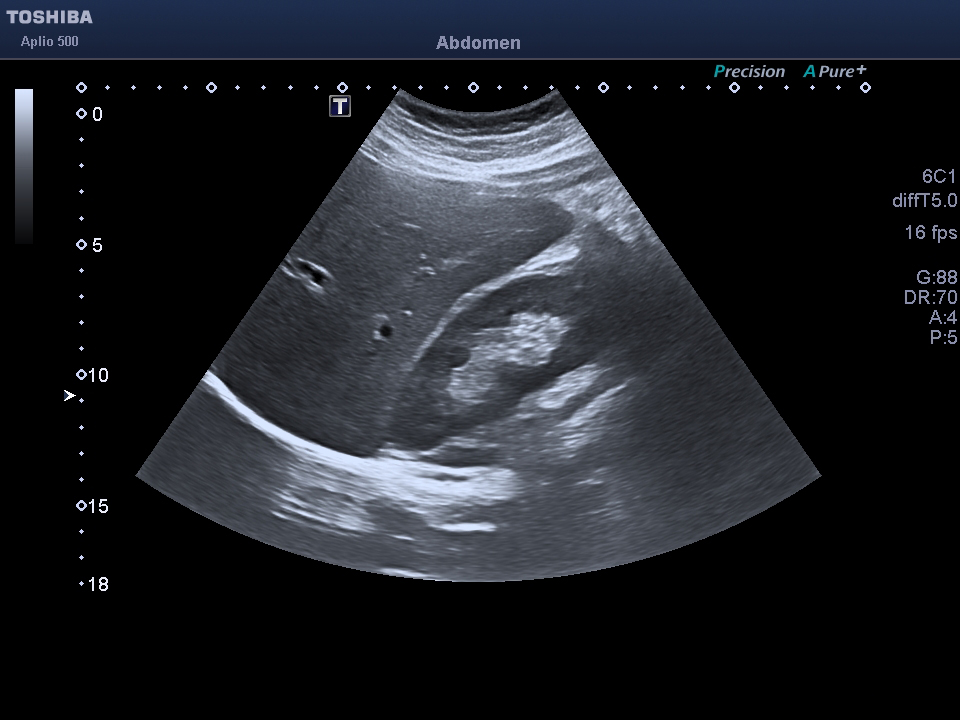

Liver phantom with multiple focal lesions including hemangioma, hepatocellular carcinoma, cyst, and metastasis for...